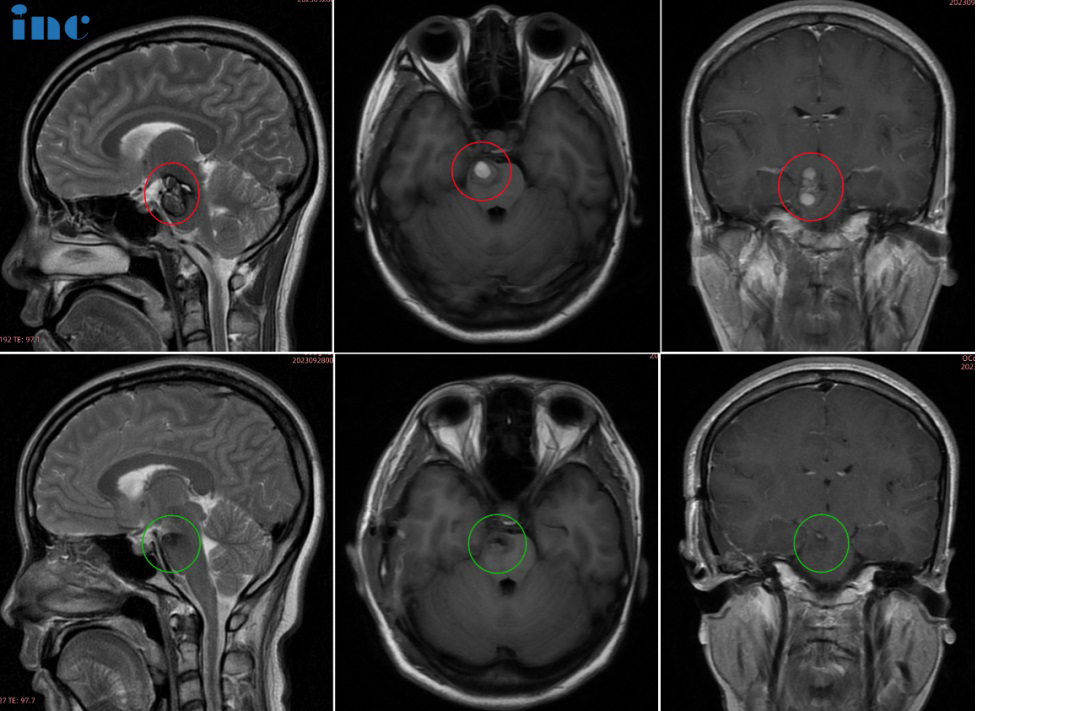

术前情况:30岁的萱萱2023年3月查出中脑及桥脑右侧占位海绵状血管瘤继发出血。当地医生考虑手术风险大,偏瘫几率大,建议保守治疗。和很多年轻的脑干海绵状血管瘤女性患者一样,当她们步入婚姻自然的要迎接新的小生命。但这一直虎视眈眈的脑干海绵状血管瘤一旦伺机而动如出现急性脑干出血,而致患者和胎儿于困境中,又该怎么办?萱萱多方打听之后,了解到在脑干海绵状血管瘤治疗领域一位国际神外教授巴特朗菲教授。

治疗过程:9月27日,在苏州独墅湖医院,巴教授顺利全切手术,手术后无瘫痪、无视神经损伤、无呼吸控制和昏迷风险。

术后情况:术后当天巴教授前往ICU查房时,已拔除气管插管、已苏醒。萱萱感激说道:“I can see,I can feel,I can move,I have power.”术后一天查房时,萱萱激动地说:“That’s amazing,I feel normal,as the same as(I did the surgery before).So amazing.(这太神奇了,我感觉我和正常无异,和术前无症状时一模一样。太神奇了)”

术后2天查房,教授查看患者切口恢复情况。

术后4天查房,恢复越来越好的萱萱问道自己术前很关心的问题——能不能准备顺利备孕,“Can I safely prepare to have a child?”“I think so,yeah”,巴教授告知萱萱脑干海绵状血管瘤已经全切了,备孕可以的。

术后6天,萱萱下地行走自如,巴教授检查了萱萱的手术切口,开心跟萱萱说“very good,even nobody can see”,萱萱也和爱人一起为巴教授点赞,合影留念。目前已出院。